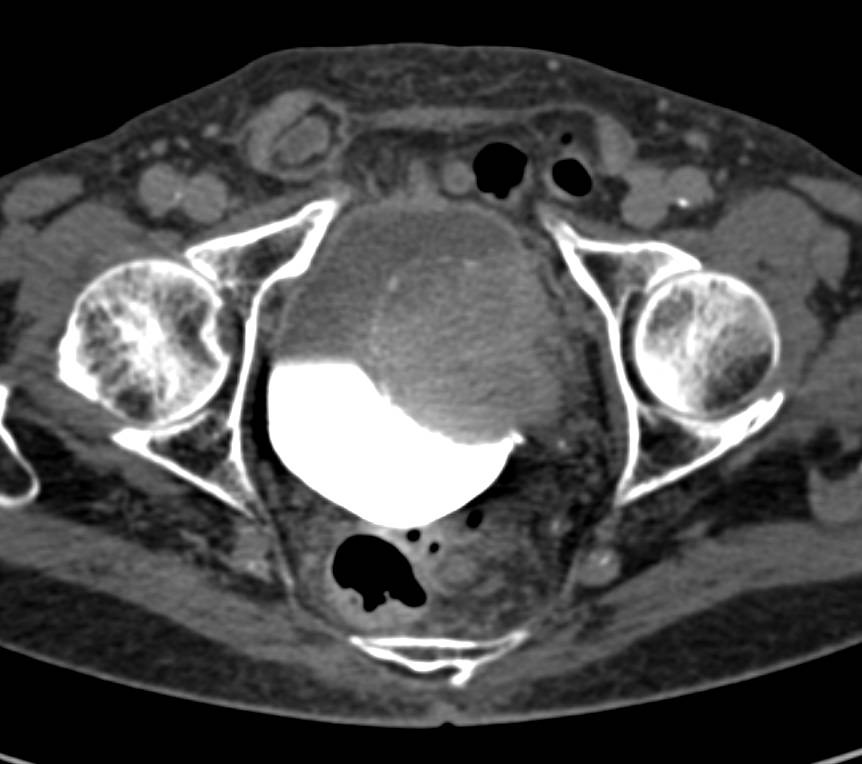

CT scan showing the location of bladder tumor. | Download Scientific …

Urothelial carcinoma of the bladder in a 59-year-old man. CT image …

Bladder cancer CT – wikidoc

Bladder Cancer with CT Urography – Genitourinary Case Studies – CTisus …

CT scan of Case 1: bladder cancer mass with associated left …

CT scan showing bladder wall thickening (arrow) and decrease in tumor …

Bladder Cancer Seen Nicely on Arterial Phase Imaging but also on CT …

Bladder Cancer with CT Urography – Genitourinary Case Studies – CTisus …